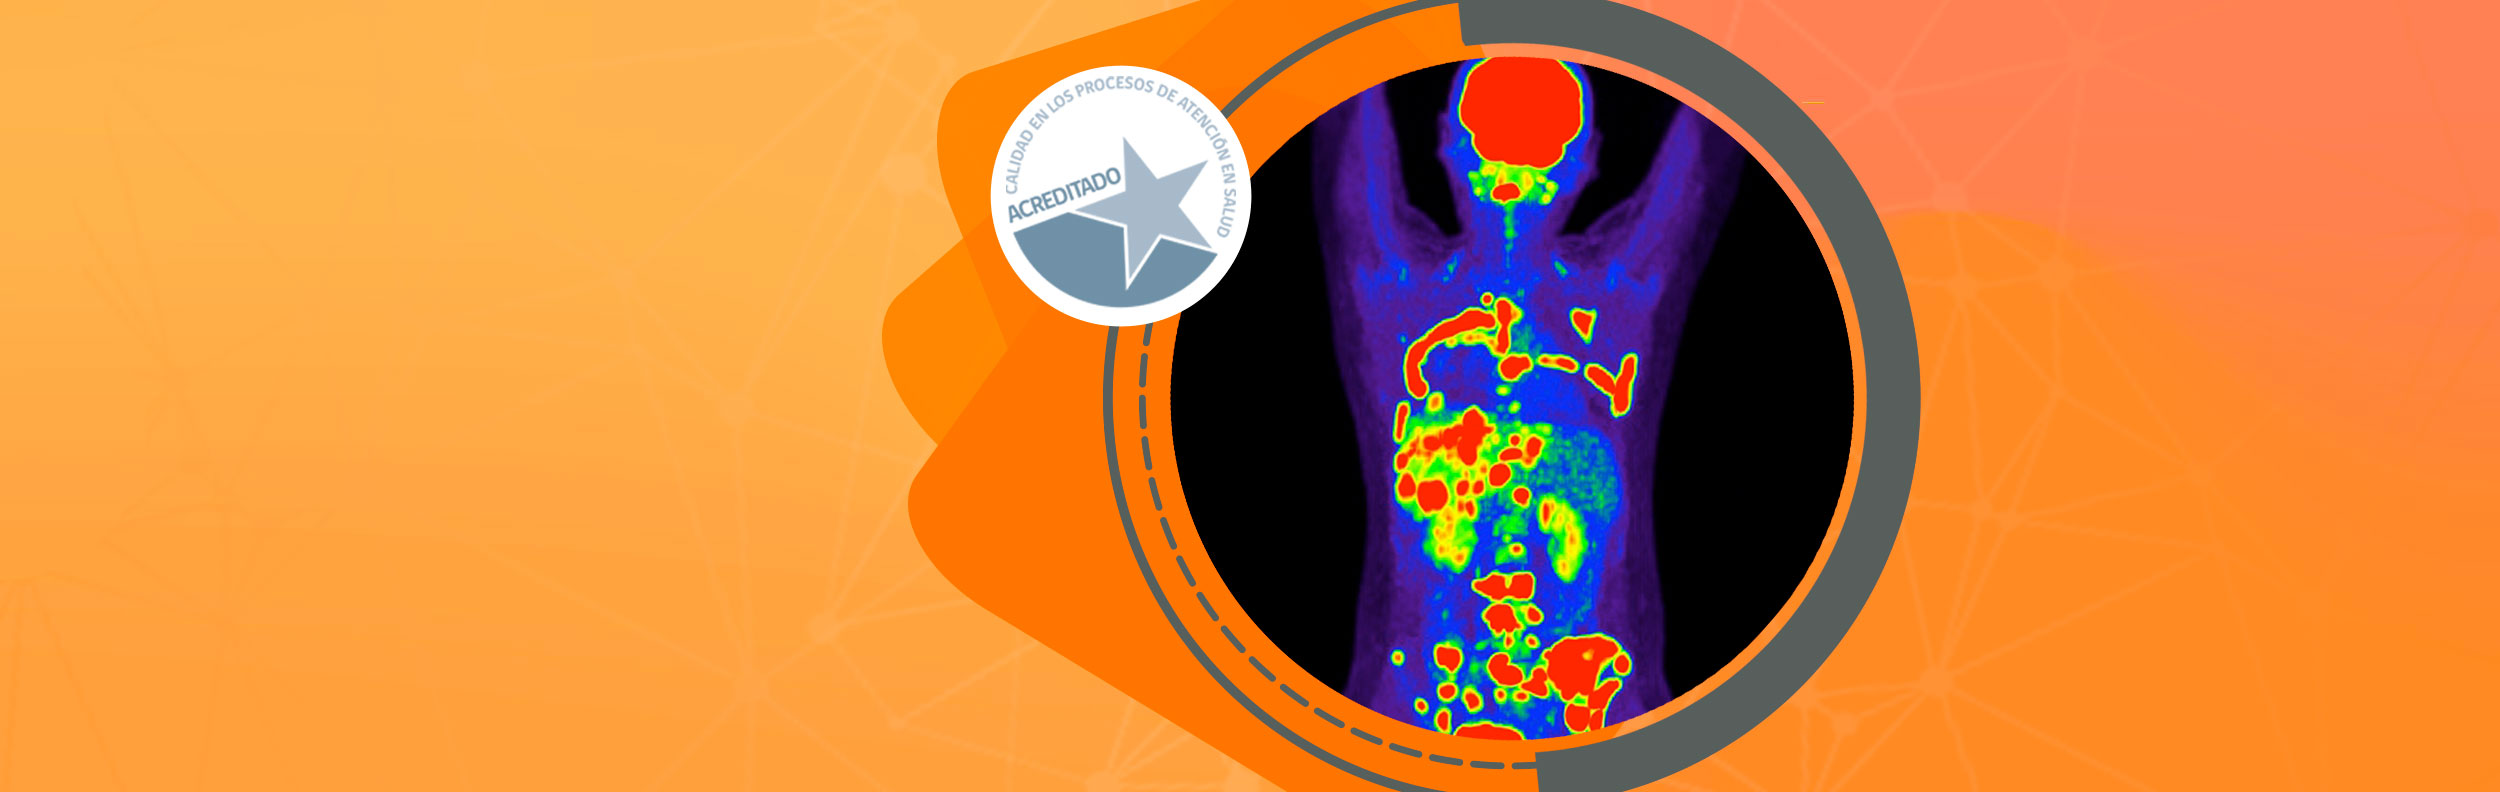

Nacemos en la ciudad de Rancagua como uno de los centros de imagenología más modernos de la región de O'Higgins. Ofrecemos una amplia gama de servicios de exámenes con tecnología de vanguardia, incluyendo TAC de 128 canales, Resonancia Magnética de 3 Teslas y PET-CT.

Nuestro compromiso con la mejora continua en la calidad de las imágenes y nuestra capacidad médico-técnica nos permite ofrecer diagnósticos más precisos, beneficiando tanto a médicos especialistas como a nuestros pacientes. Como referentes en diagnóstico médico, somos el único centro acreditado de la región en procesos de atención en salud en imagenología médica.